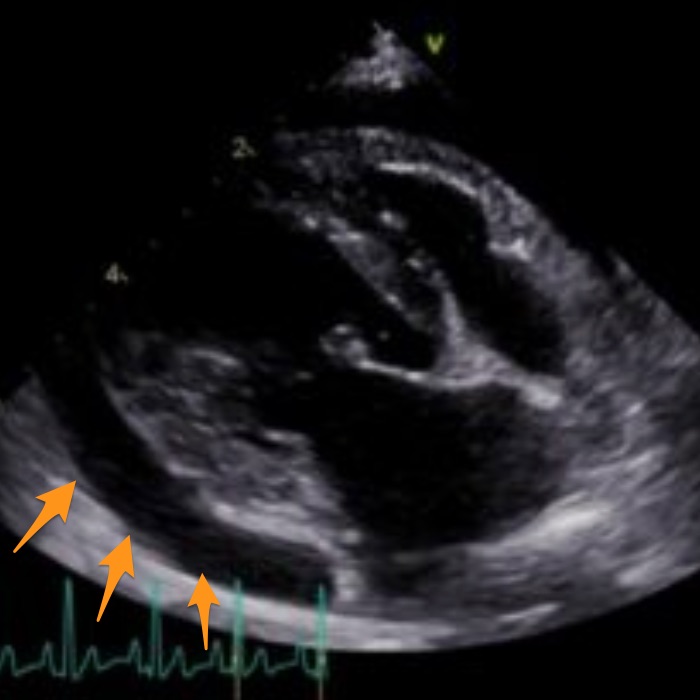

本コラムでは獣医療の専門的な情報を取り扱っており、手術中の写真など刺激を受ける可能性のある医療画像を含む場合があります。